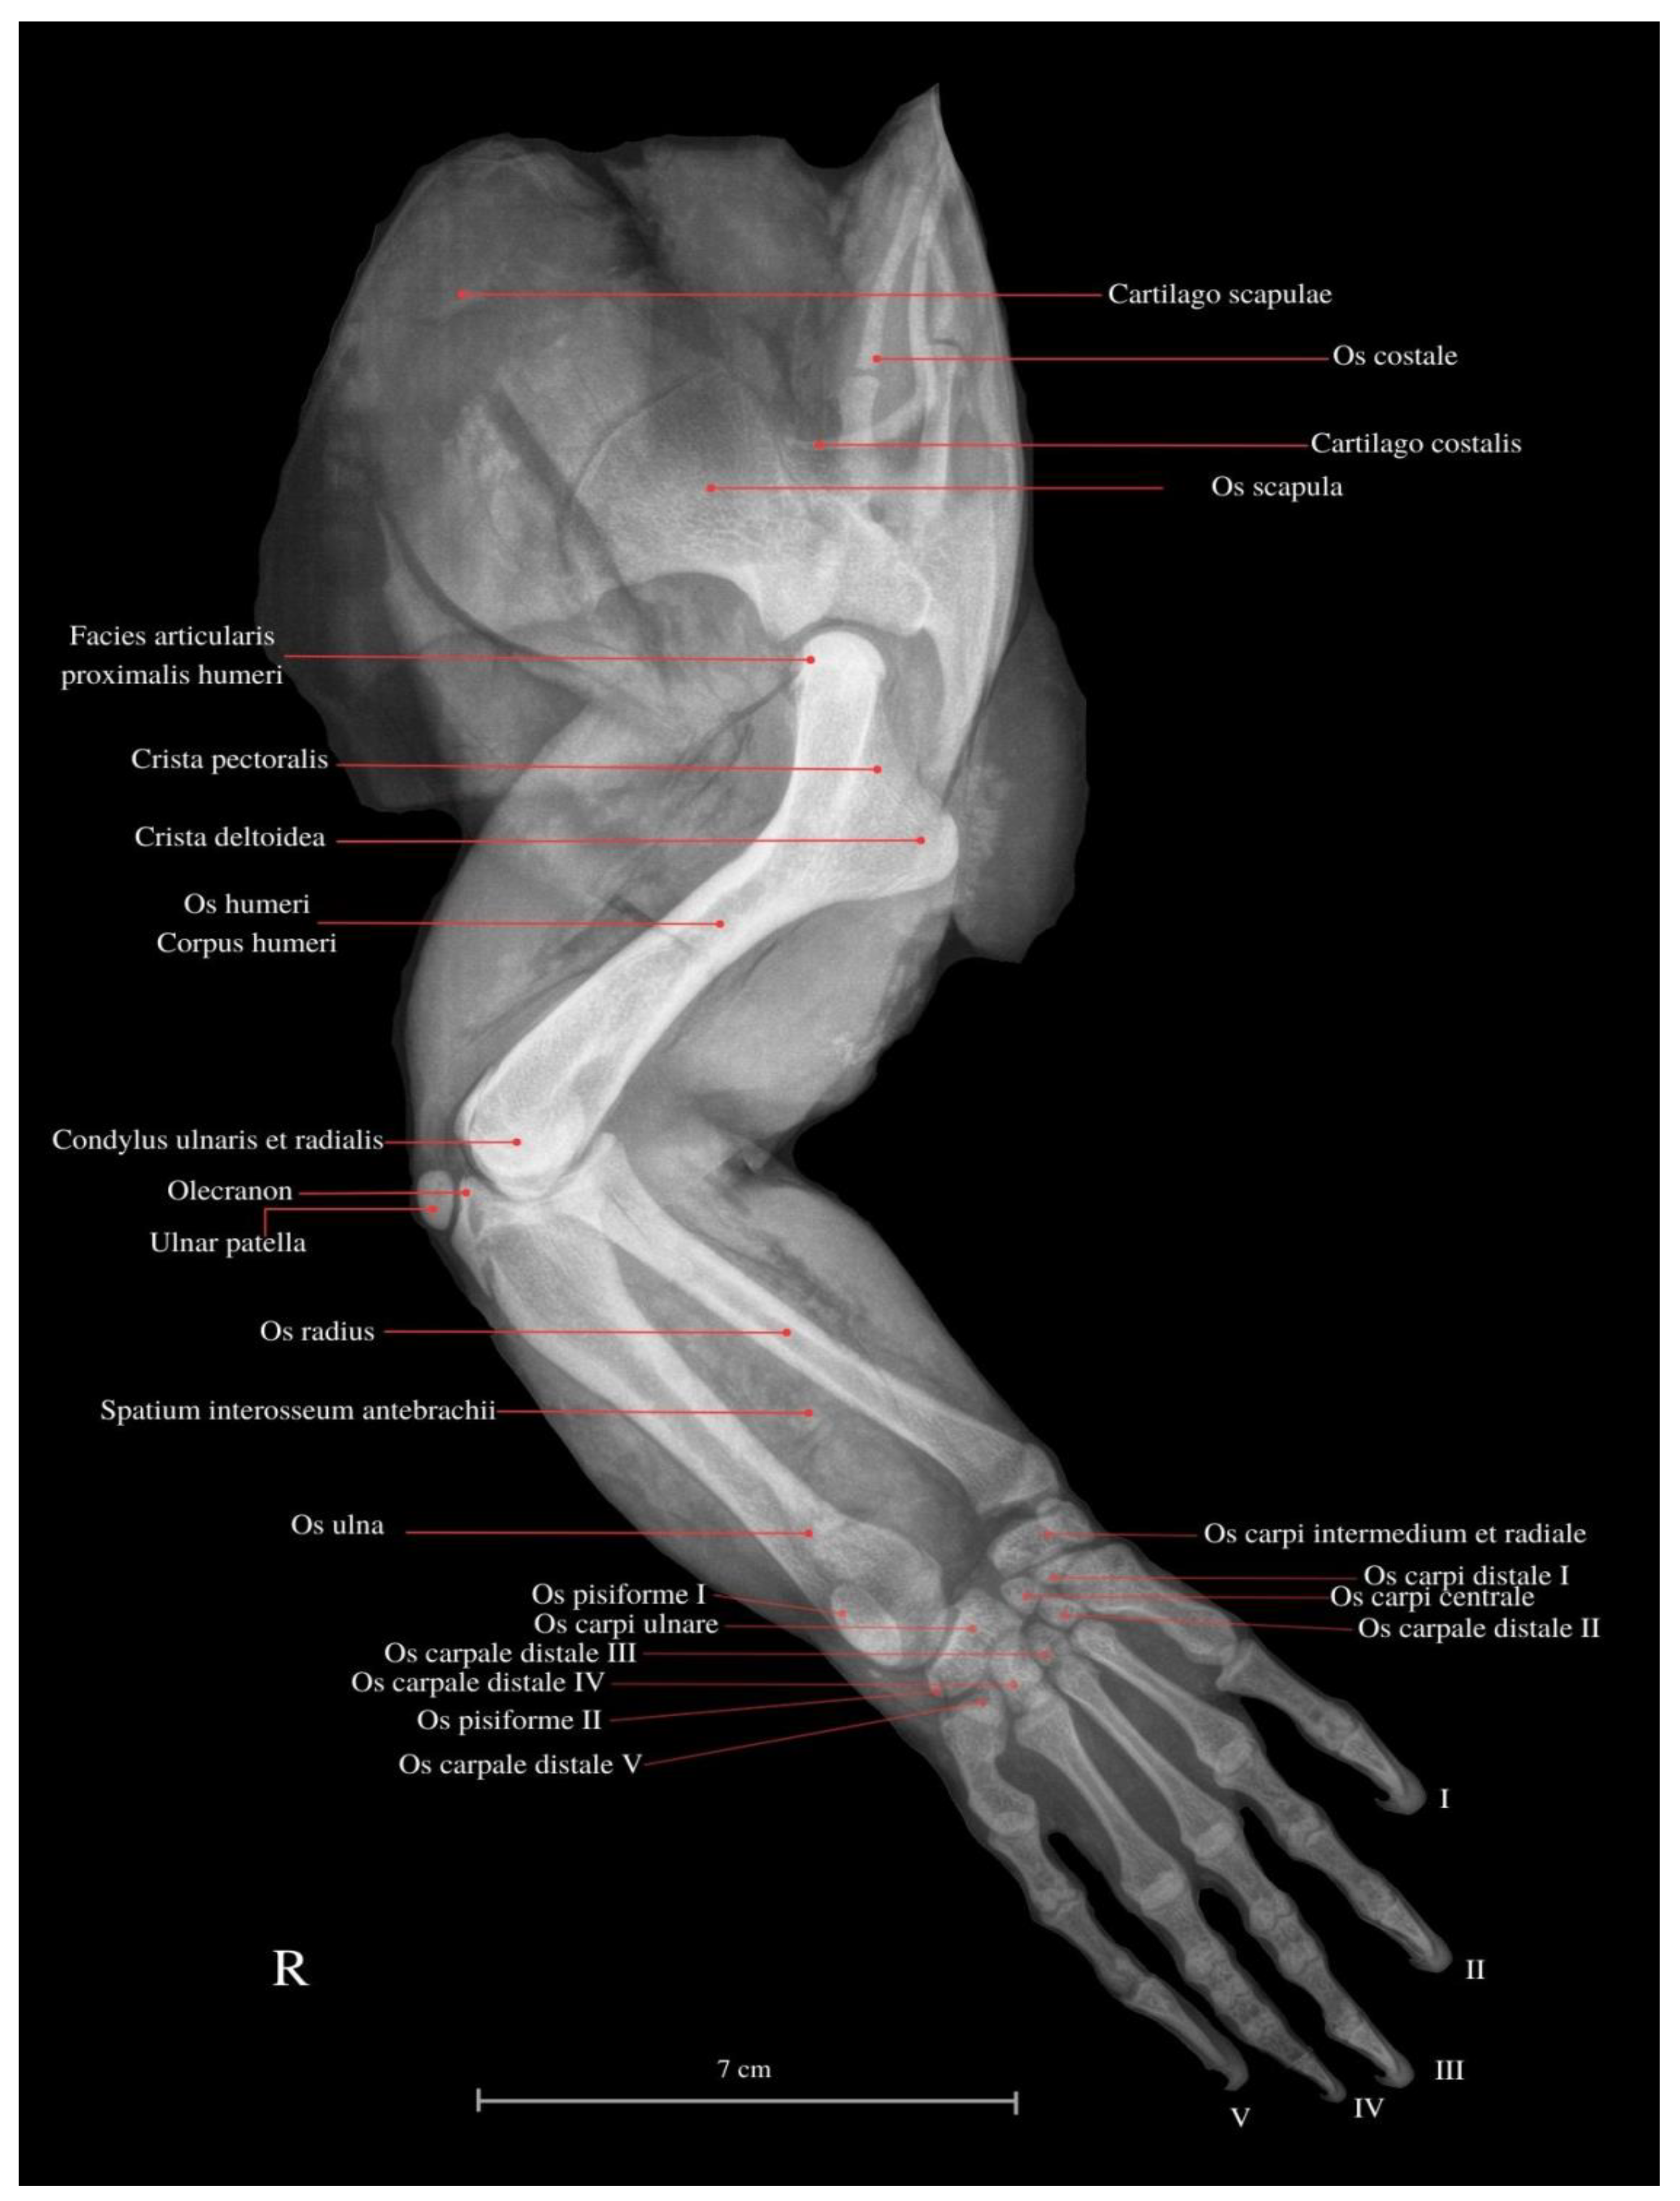

Functional Anatomy of the Thoracic Limb of the Komodo Dragon (Varanus komodoensis)

3. Results

- Fakhrian, A.M.; Pamungkas, J. Nurhidayat. Komparasi Karakteristik Anatomi Skelet Ekstermitas Kaki Depan Komodo (Varanus komodoensis) degan Biawak Air (Varanus salvator); Skripsi; IPB University: Bogor, Indonesia, 2023. [Google Scholar]

- International Committe on Veterinary Gross Anatomical Nomenclature (I.C.V.G.A.N.). Nomina Anatomica Veterinaria, 6th ed.; Editorial Committee: Hanover, Germany; Ghent, Belgium; Colombia, MO, USA; Rio de Janeiro, Brazil, 2017. [Google Scholar]

- El-Bakry, A.M.; Abdeen, A.M.; Abo-Eleneen, R.E. Comparative study of the osteology and locomotion of some reptilian species. Int. J. Biol. Biol. Sci. 2013, 2, 40–58. [Google Scholar]